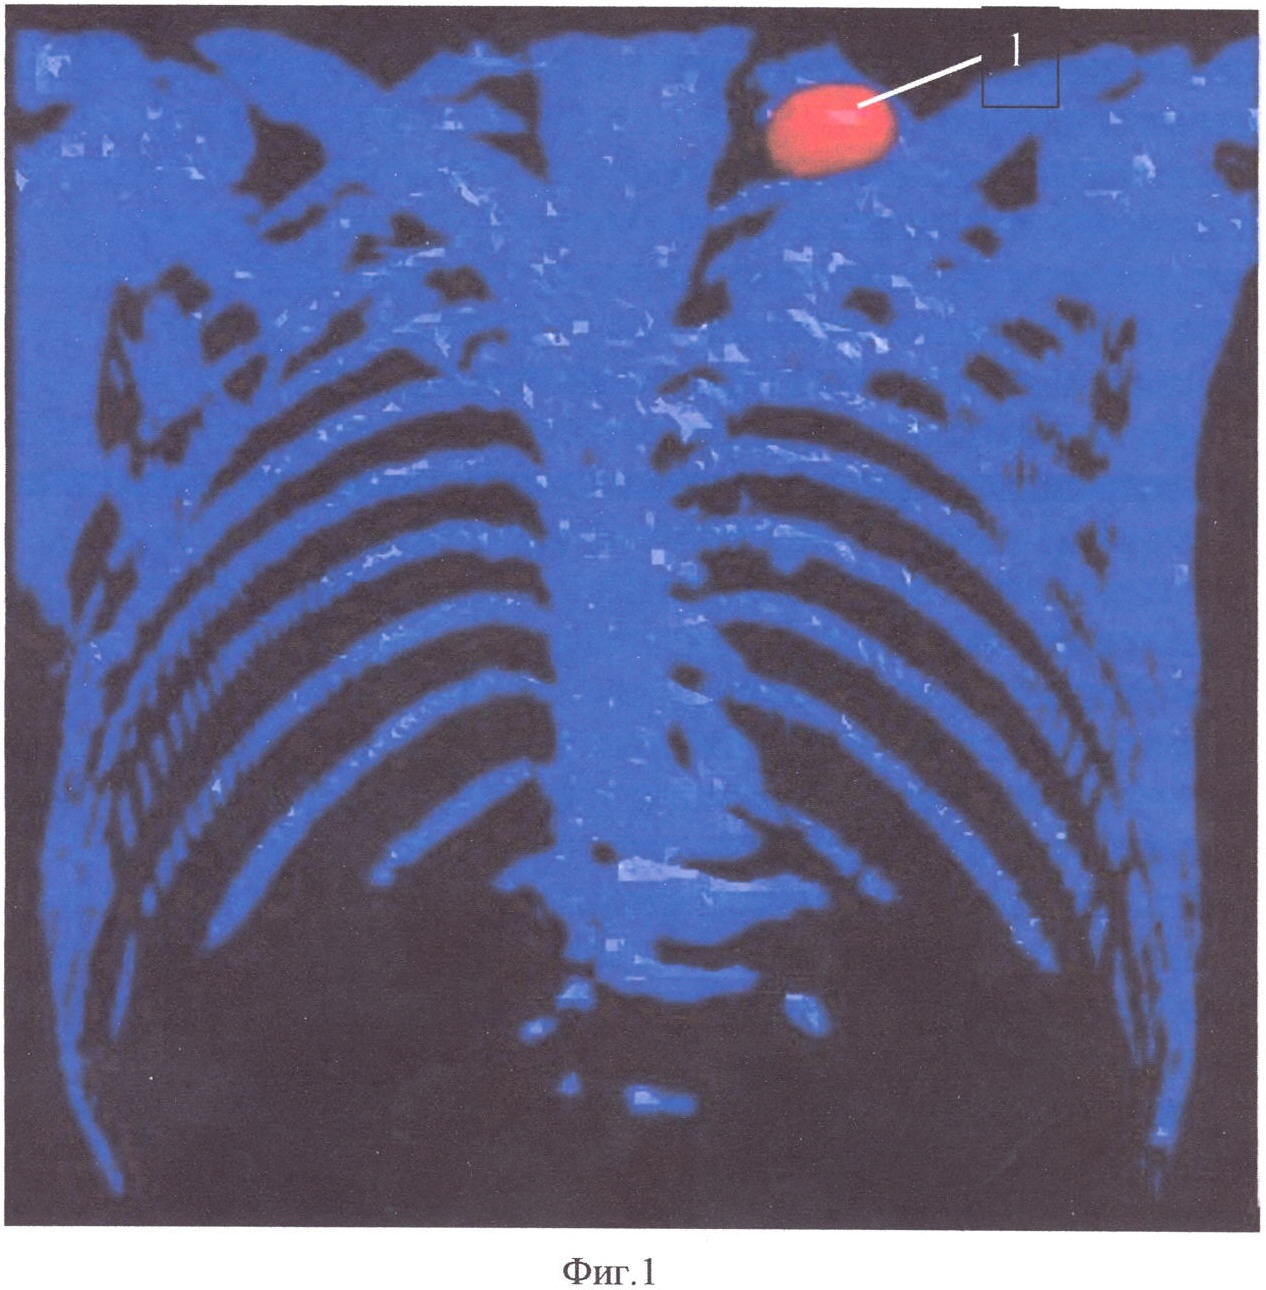

На фиг.1 представлено изображение радиоактивной метки, расположенной на средней трети ключицы в совмещенном трехмерном изображении легких, на фиг.2 представлен аксиальный срез легких на однофотонном компьютерном томографе, где видны участки редуцированного кровотока, на фиг.3 представлен аксиальный срез легких на компьютерном томографе того же уровня, как на ОФЭКТ, где видны участки наибольшего поражения легочной паренхимы, на фиг.4 представлено совмещенное изображение аксиального среза легких.

На этапе 1 больному выполняют ОФЭКТ на двухдетекторной гамма-камере Philips Forte 2005 (USA). Внутривенно вводят радиофармацевтический препарат (РФП), представляющий собой крупные белковые частицы, меченные радионуклидом (гамма-излучателем) и вызывающие временную эмболизацию артериоло-капиллярного русла легких в дозе 1,0-1,5 мБк на 1 кг веса тела исследуемого. Для последующей синхронизации изображения ОФЭКТ и МСКТ на область средней трети ключицы устанавливают (2 мБк-Тс 99m) радиоактивную метку 1 (фиг.1).

Пациент А., 1939 года рождения, поступил в отделение пульмонологии в экстренном порядке с жалобами на слабость, нарастающую отдышку, повышение температуры тела. В анамнезе имели место эпизоды кровохарканья. Для исключения тромбоэмболии легочной артерии (ТЭЛА) была выполнена ОФЭКТ легких с предварительным нанесением радиоактивной метки (2 мБк) 1 на область средней трети ключицы (фиг.1). Исследование выполнялось по стандартной методике. По данным радиологического исследования выявлено снижение перфузии в правом легком в проекции S 6, 10 и в плащевом отделе верхних долей как справа, так и слева. В проекции S 4, 5 обоих легких выявлены дефекты перфузии 2, по форме близкие треугольной (фиг.2). Предварительный диагноз: Тромбоэмболия мелких ветвей легочной артерии, косвенные признаки бронхиальной обструкции.